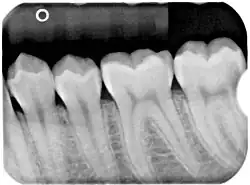

Periapical radiograph(figure 2)

Panoramic(figure 1) and apical(figure 2) radiographs are commonly utilised in routine examinations to aid in the initial detection of BBC.[15] BBC is characterised by a well-defined radiolucent lesion on the buccal aspect of the tooth extending from furcation to the root apices.[19][20] With the presence of periosteal reaction on the buccal aspect of the tooth.[21][22] Tilting of the affected molars, with the apices of the roots tilted lingually and cusp tip buccally.[21][22] Unlike a periapical cyst, the periodontal ligament space and lamina dura remain intact and continuous, suggesting that the lesion is not directly associated with the root apices.[15][21][22]